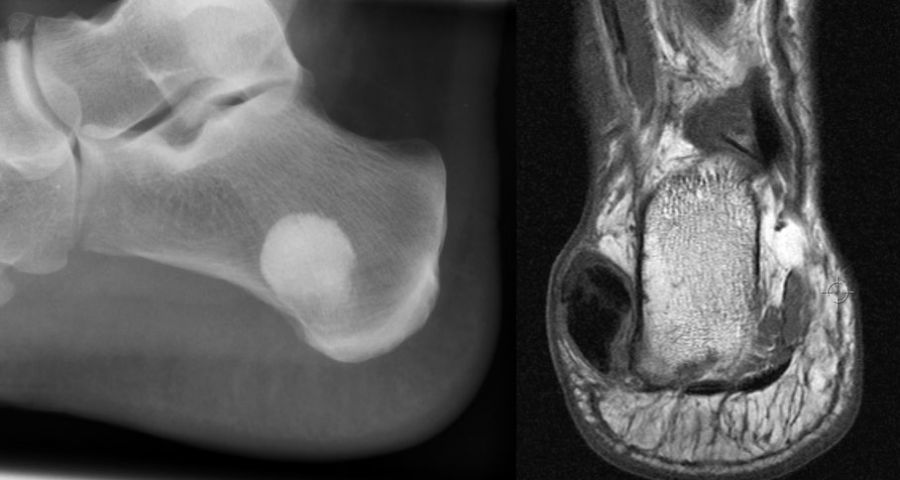

Die juvenile Knochenzyste (Syn. Solitäre Knochenzyste) findet sich am Fuß fast ausschließlich am Calcaneus im Bereich des Ward´schen Dreieckes bzw. im ventralen triangulären Bereich zwischen den Haupttrabekelgruppen (Diard´s Area 6) 3536. Eine physiologische Rarefi­zierung der Trabekelstrukturen in diesem Bereich muss strikt von tumorösen Raumforde­rungen differenziert werden 3738. Die Hauptindikation einer operativen Therapie stellen Schmerzen und eine drohende pathologische Fraktur dar (Abb. 23). Calcaneuszysten, die in der Koronarebene 100% des Querschnitts erreichen oder 30% der Sagittalebene einneh­men, gelten als potentiell frakturgefährdet und sollten auch bei Symptomfreiheit prophylak­tisch operiert werden 3940 (Abb. 24). Da simple Knochenzysten nicht selten als radiolo­gischer Zufallsbefund auffallen, kann auch die Tumorangst des Patienten eine Indikation darstellen. Eine differenzierte Aufklärung des betroffenen Patienten (und seiner Eltern) ist hier umso mehr erforderlich.

Sobald eine osteolytische Knochenläsion des Calcaneus erscheint, ist eine weiterführende Abklärung mittels MRT indiziert. Das intraossäre Lipom des Calcaneus lässt sich im Röntgen nur dann von der simplen Knochenzyste unterscheiden, wenn zentrale, dystrophe Verkal­kungen vorliegen (Abb. 25). Diese auch als Nidus oder Sequestrum bezeichneten Kalzifi­kationen sind typisch, jedoch nicht obligat für das intraossäre Lipom.